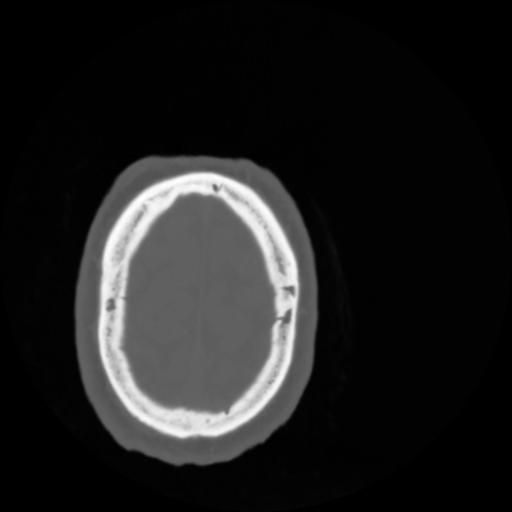

4 CEREBRO,,Vol,0.5,CEREBRO,,